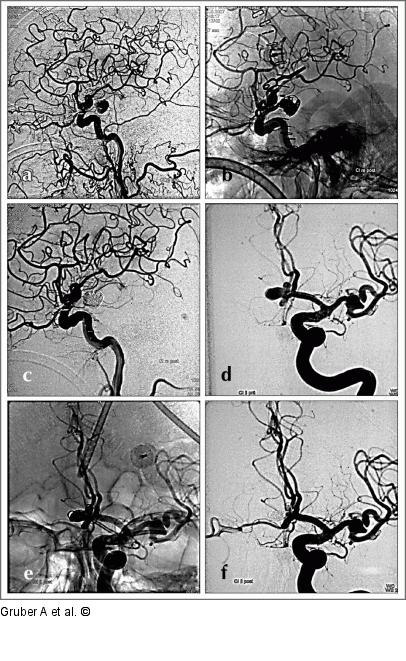

Abbildung 6a-f: Coil nach Clip "Coil nach Clip". Beispiele für endovaskuläre Coil-Embolisation bei Rest- (a–c) bzw. Rezidivaneurysmen (d–f) nach mikrochirurgischer Therapie. Coil-Embolisation von Aneurysmarest 2 Wochen nach Klippung eines rupturierten Aneurysmas der A. carotis interna rechts am Abgang der A. communicans posterior (a–c). Coil-Embolisation von Aneurysmarezidiv 8 Jahre nach Klippung von blandem Aneurysma der A. communicans anterior (d–f). An der linken A. cerebri media findet sich nach chirurgischer Klippung eines Riesenaneurysmas und Clip-Rekonstruktion der Mediabifurkation am ehemaligen Aneurysmahals ein kleines schüsselförmiges Residuum. |

"Coil nach Clip". Beispiele für endovaskuläre Coil-Embolisation bei Rest- (a–c) bzw. Rezidivaneurysmen (d–f) nach mikrochirurgischer Therapie. Coil-Embolisation von Aneurysmarest 2 Wochen nach Klippung eines rupturierten Aneurysmas der A. carotis interna rechts am Abgang der A. communicans posterior (a–c). Coil-Embolisation von Aneurysmarezidiv 8 Jahre nach Klippung von blandem Aneurysma der A. communicans anterior (d–f). An der linken A. cerebri media findet sich nach chirurgischer Klippung eines Riesenaneurysmas und Clip-Rekonstruktion der Mediabifurkation am ehemaligen Aneurysmahals ein kleines schüsselförmiges Residuum. |